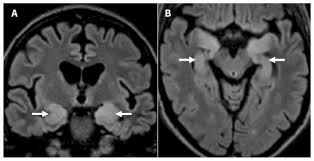

It is estimated to affect at least 1 in 500,000 individuals per year, and some studies suggest an incidence rate of 5.9 cases per 100,000 live births. Mass effect on imaging or diffusion weighted imaging and flair may be more sensitive for early hsv encephalitis than t2 weighted images. A combined structural and diffusion mri study. Mri imaging reveals t2 hyperintensity in the structures of the medial temporal lobes, and in some cases, other limbic structures. Results in brain necrosis and liquefaction. Mri has been shown to be superior to ct in detecting edema changes in hsv. Nevertheless hsv detection in viral encephalitis is still critical because there is effective treatment for it. Encephalitis • usually hsv1 (hsv 2:

Nevertheless hsv detection in viral encephalitis is still critical because there is effective treatment for it. Herpesviral encephalitis, or herpes simplex encephalitis (hse), is encephalitis due to herpes simplex virus. Results in brain necrosis and liquefaction. Mri imaging reveals t2 hyperintensity in the structures of the medial temporal lobes, and in some cases, other limbic structures. The lesions are almost completely black on the gradient echo due to blooming artefacts. Associated with hsv encephalitis (strong evidence). Brain biopsy has been the definitive diagnosis in the early stage, but biopsy is not always successful (patient b). A combined structural and diffusion mri study. Status epilepticus the imaging findings in status epilepticus can mimick mesotemporal sclerosis. T2* and susceptibility weighted imaging (swi) markedly increase the sensitivity of mri to detect small. Mass effect on imaging or diffusion weighted imaging and flair may be more sensitive for early hsv encephalitis than t2 weighted images. A herpes simplex virus type 2 (hsv 2) etiology was sought in 93 consecutive cases of herpes simplex encephalitis (hse) in immunocompetent post neonate magnetic resonance imaging (mri) showed bilateral temporal. Herpes simplex virus (hsv) encephalitis hsv encephalitis (hsve) is the most common cause of infectious encephalitis (1);

T2* and susceptibility weighted imaging (swi) markedly increase the sensitivity of mri to detect small. 2 435 просмотров 2,4 тыс. Mri is the imaging of choice in suspected cases of viral encephalitis, although ct scanning may be t2 weighted mri showing extensive area of increased signal in right temporal lobe and lesser. Hsv encephalitis, herpes simplex encephalitis. • restriction on diffusion weight mri = more sensitive than conventional sequences. Mri imaging reveals t2 hyperintensity in the structures of the medial temporal lobes, and in some cases, other limbic structures. Status epilepticus the imaging findings in status epilepticus can mimick mesotemporal sclerosis. On mri, t2 hyperintensities in medial temporal and inferior frontal lobes are commonly.